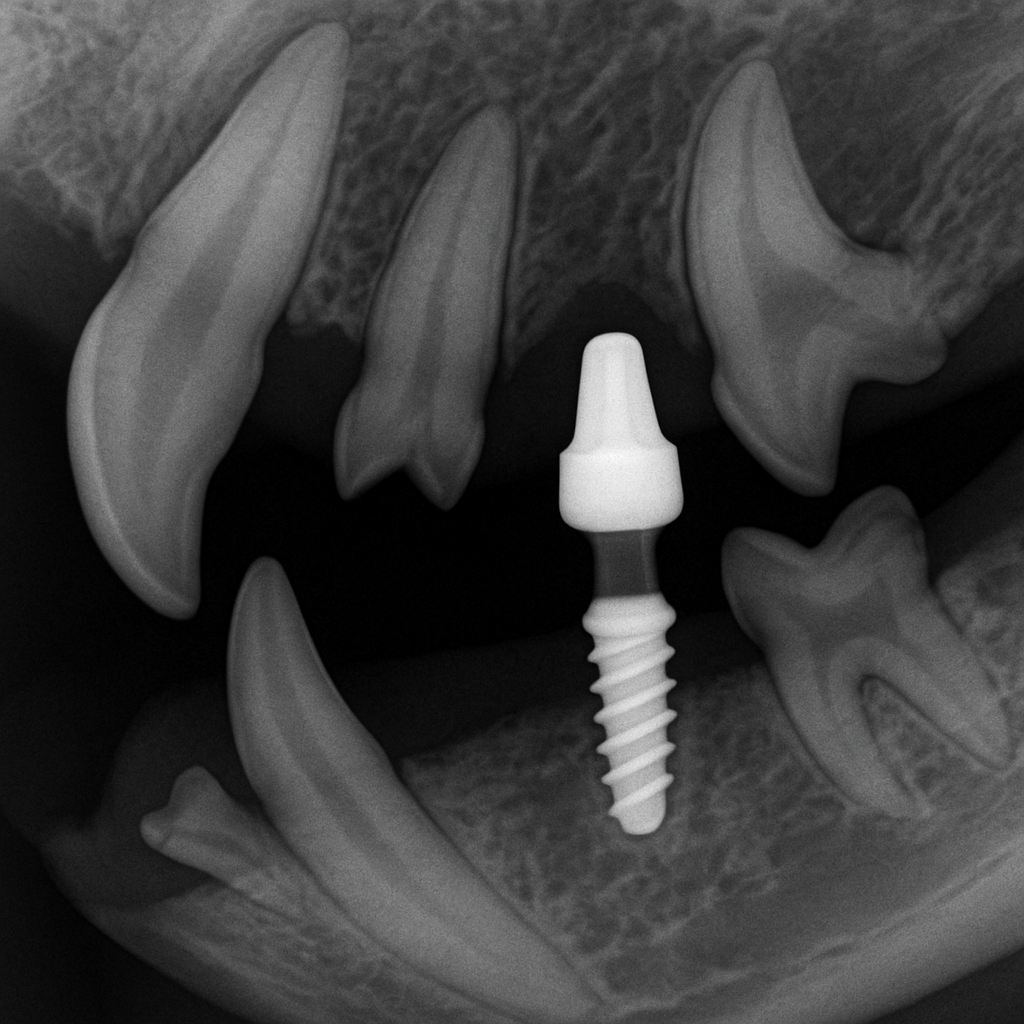

강아지 임플란트는 잃어버린 치아 부위에 인공 치근을 식립한 후 보철물을 고정해 치아 기능을 대신하는 시술입니다. 시술 순서는 다음과 같습니다.

- 구강 상태 검사 및 X-ray 촬영

- 전신 마취 후 인공 치근 식립

- 약 2~4개월간 인공 치근과 턱뼈 유착 기간

- 인공 치관(보철 치아) 장착

인체용 임플란트와 구조는 유사하지만, 강아지는 턱뼈 크기와 형태가 다르기 때문에 수의치과 전문의의 경험이 매우 중요합니다.